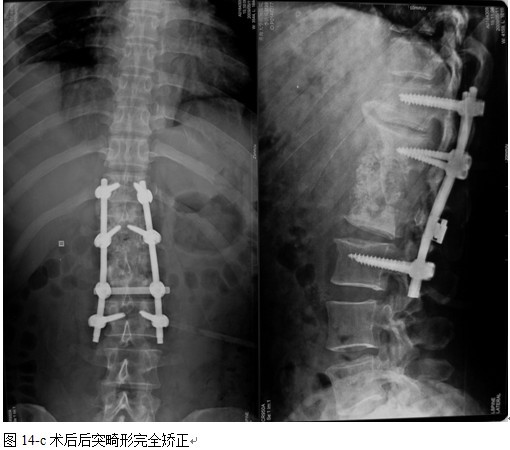

结果: 术后所有患者均显示,骨性融合, 马尾神经损伤的患者均基本恢复正常,术后后凸畸形平均矫正90%以上, 3-49个月的随访,后凸角度平均丢失4.2°。

本组手术用时间3~4h , 平均3.5h 。术中出血300~500ml , 平均约350ml 。术后症状完全缓解,无神经功能障碍加重等并发症,1例营养差的老年患者伤口出现窦道,1例因肝功能差,术后未口服抗痨药,伤口出现窦道,经换药后二期愈合,其余病例伤口均一期愈合。马尾神经受损的患者术后基本恢复正常。术后一周后凸角平均 5.4°后凸畸形平均矫正90%以上, 最终后凸角平均8.3°,后凸角度平均丢失4.2°。随访3个月有87%(40/46)有骨痂形成,6个月91.3%(42/46)明显骨性愈合(见图),其余4例9-12个月内愈合,随访时间3-32个月,平均11个月,46例患者中2例在术后2个月和3个月时背部形成脓肿,换药后治愈。2例出院1月后并发结核性脑膜炎,治疗后好转。1例因椎弓根钉偏外,刺激神经根,5个月后从侧方脱出,疼痛加重,因前后路植骨完全愈合,取出后症状完全缓解。

中国学者金大地[22]等采用一期前路病灶清除植骨前路钢板固定治疗腰椎结核,平均18°的后凸畸形得以矫正,Mukhtar[23] AM等采用前路病灶清除植骨分期或同期后路固定治疗腰椎结核22例,术后后凸畸形矫正度数平均为27°。从我们的随访结果看,术后后凸畸形平均矫正度数为26.9°,后凸畸形平均矫正90%以上, 6个月-49个月后随访,后凸角度平均丢失4.2°。本术式也适用于结核所引起的弹性差的后凸畸形,对于病灶纤维化或骨化的非弹性后凸畸形,后路固定后,先行前路病灶、纤维化或骨化切除、松解,逐步刮除病灶、逐步撑开,达到畸形矫正和植骨的目的。

此术式的特色与创新之处⑴创伤小,但显露病变清晰,视野和操作空间满意;⑵内固定避开直接接触感染病灶,安全性更有保障;⑶前路清除病灶减压后纠正畸形,可前后方同时纠正畸形,畸形矫正率非常高,避免了纠正畸形时病灶挤压硬膜。360°植骨使融合率提高而且防止和减少矫正率的丢失;⑷手术一次完成,且不干扰胸腹腔有利于术后治疗护理,医疗费用低于前路一期手术者;⑸对于复杂僵硬后凸畸形患者,还可以同期楔形截骨矫形,提高矫形成功机会。但此术式操作中的困难之处:植骨块的放入,并发症就是放植骨块时对神经根的损伤。